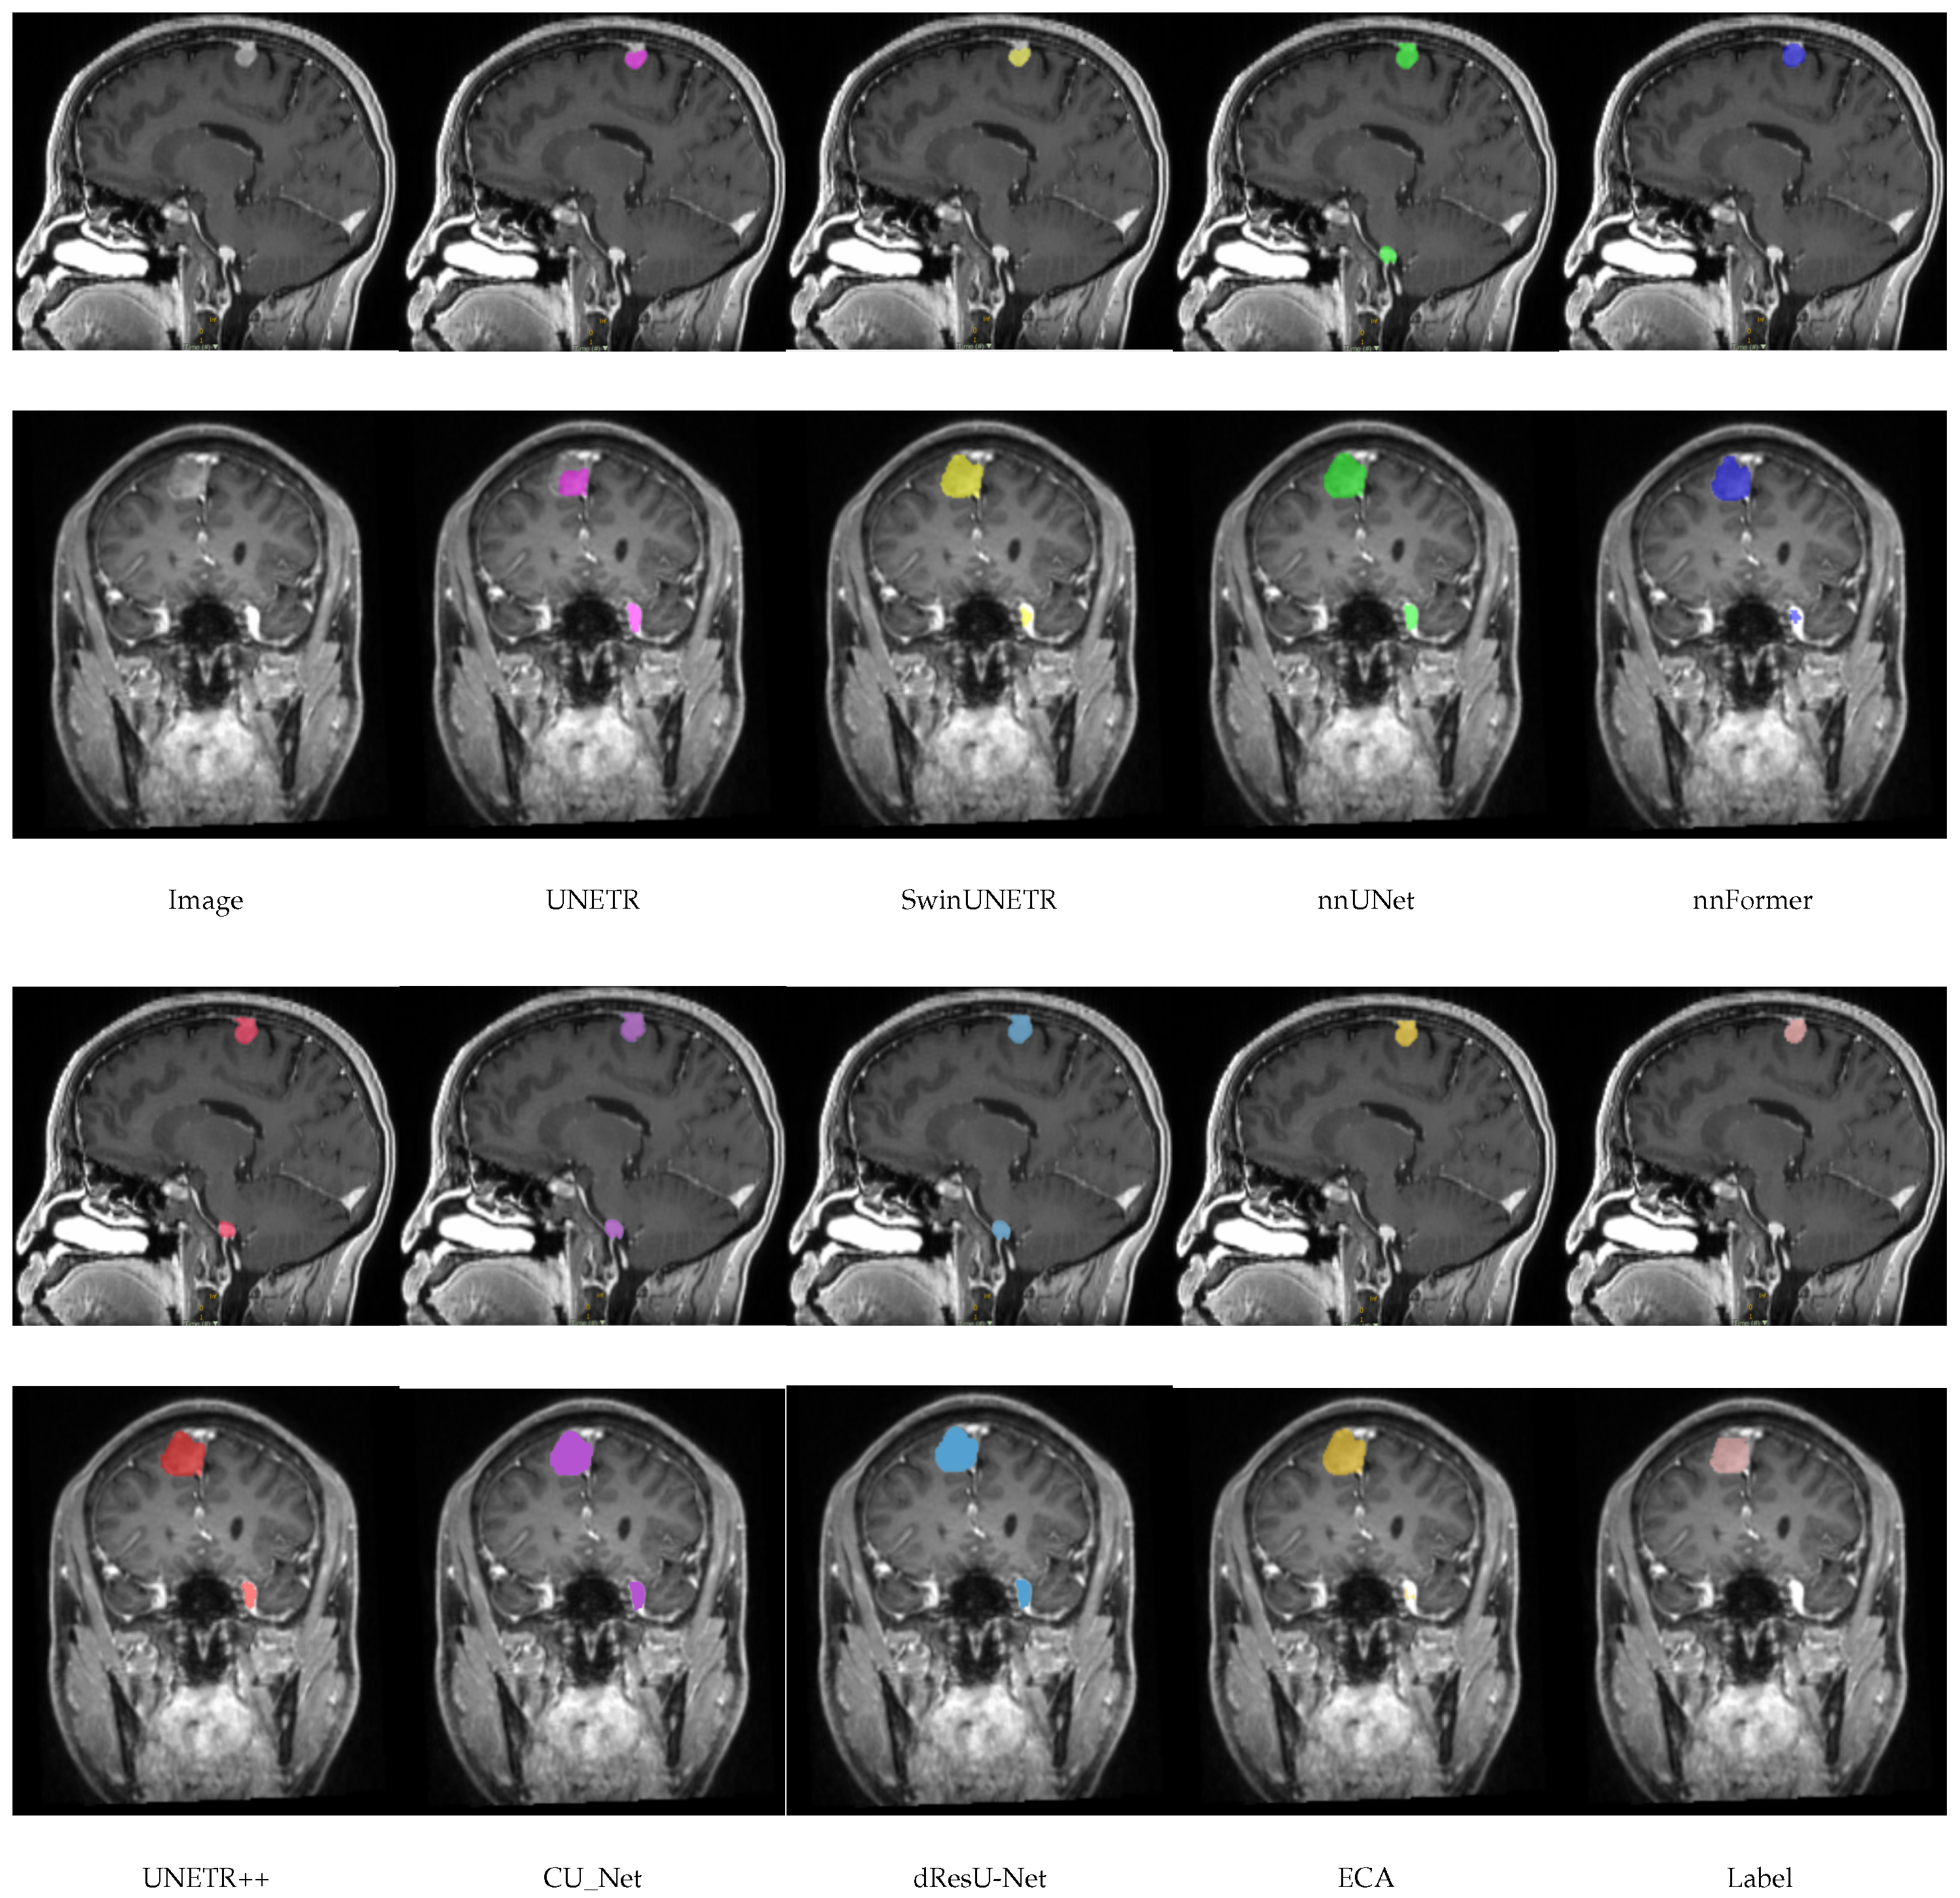

In this section, a comparison of the predictions of the ECA model with other models on the meningioma dataset is shown in Figure 4. By comparing the segmentation of each model, it can be seen that there are significant differences in the accuracy and boundary clarity of the different models in meningioma segmentation. UNETR’s predictions are unclear at the boundaries, and its segmentation areas are small, failing to segment the whole tumor. In addition, there is an obvious error in SwinUNETR, nnFormer, nnUNet, and UNETR++, that is, these models identify regions that are non-tumors as tumors. Compared with other models, the segmentation by ECA is the closest to the ground truth, especially in the meningioma regions with complex details, indicating that the feature extraction and boundary processing capabilities of ECA are superior.

Figure 4.

Visualization results of models on the meningioma dataset.